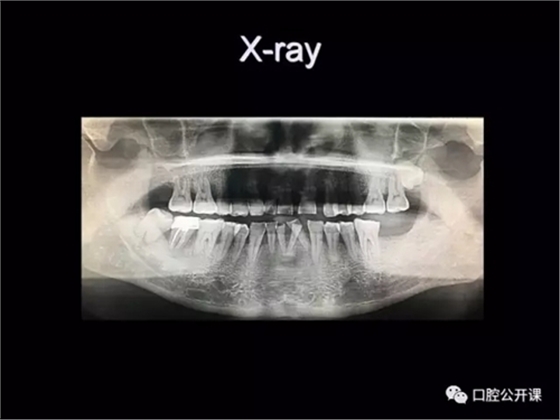

楊淑銀醫(yī)師用他的一例侵襲性牙周炎五年臨床病例追蹤來(lái)縮影一個(gè)青年牙周醫(yī)師的成長(zhǎng)之路,帶我們一起探索看似平凡枯燥的牙周基礎(chǔ)治療到底有怎樣的重要性?